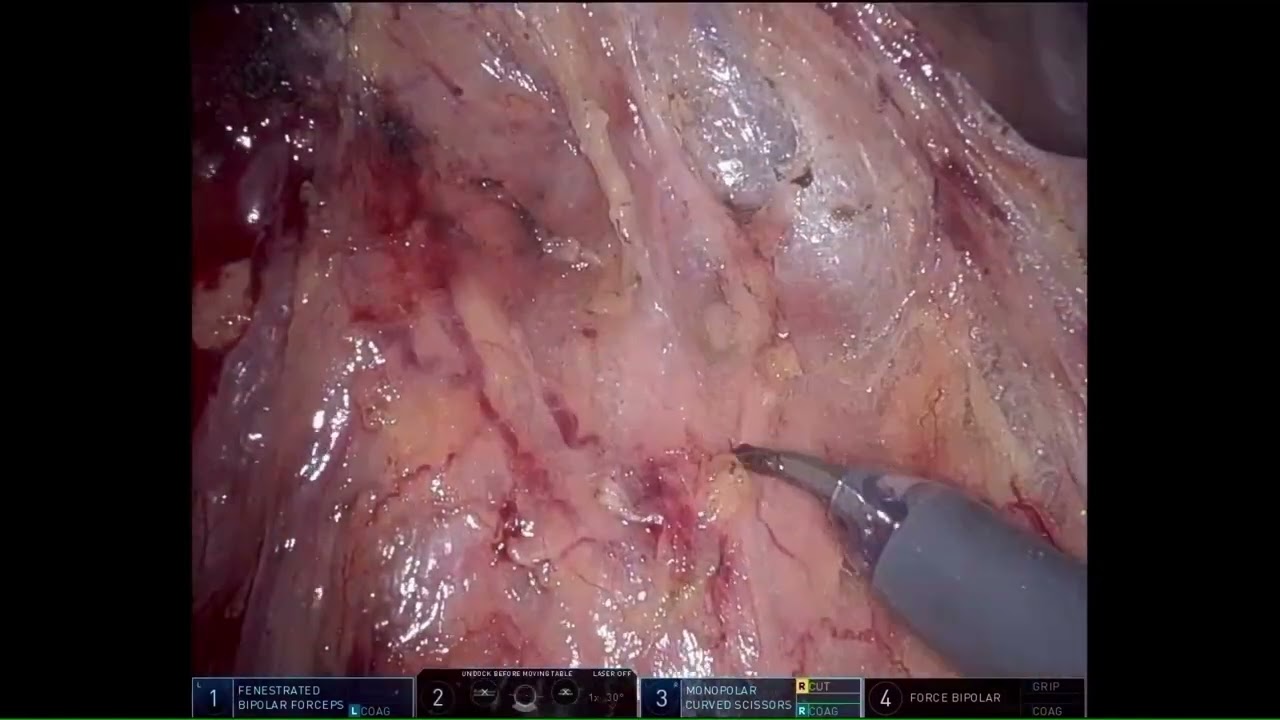

#306 Single port urinary diversion in a hostile abdomen- Dr. Neerja Tillu

KS Awards, Robotics, Surgeon ';